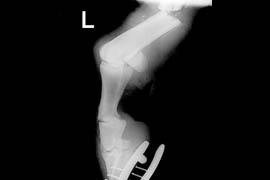

W dniu 2009.05.02 około godziny 13.00 zadzwoniła właścicielka konia Prince of Jump i poinformowała, że jej koń uległ wypadkowi komunikacyjnemu i ma złamaną tylną kończynę, następnie przekazała telefon panu Maciejowi Parzydło, organizatorowi zawodów w pobliżu miejsca wypadku, z którym przeprowadziłem wywiad dot. stanu konia i przekazałem informacje dotyczące pierwszej pomocy i zabezpieczenia kończyny. Właścicielka konia zdecydowała się podjąć próbę ratowania konia mimo bardzo ostrożnego rokowania. Poprosiłem, żeby skontaktowali się z lekarzem domowym celem zabezpieczenia konia przed dalszymi następstwami wypadku i poinstruowałem o sposobach zabezpieczenia konia w czasie transportu. Telefon o wyjeździe konia z miejsca zdarzenia odebrałem około godziny 18. Koń został przyjęty do Szpitala o godzinie 21.20. Okazało się, że nadpęcie lewej tylnej kończyny jest złamane poprzecznie i niestety ma charakter otwarty. Stan ogólny konia był ciężki ze względu na rozwijający się wstrząs. Badania laboratoryjne wskazywały na rozwój mięśniochwatu. Ze względu jednak na stan kończyny zdecydowałem o natychmiastowym wykonaniu operacji. Zabieg trwał od godziny 23.30 do godziny 03.00. W okresie poprzedzającym operację koń otrzymał leki mające zminimalizować objawy wstrząsu i intensywną terapię płynami, terapia ta była kontynuowana przez cały okres zabiegu. Po operacji kończyna została zagipsowana, koń zaś umieszczony w boksie anestezjologicznym, w którym do czasu odzyskania przezeń świadomości był dalej nawadniany. Niestety parametry laboratoryjne wskazywały na dalszy rozwój mięśniochwatu i uszkodzenie mięśnia sercowego. Stan ogólny konia pomimo leczenia nie poprawiał się, jednak leczenie było kontynuowane do godziny 03.00 dnia 04.05.2009, kiedy to nastąpiło załamanie krążenia i zgon konia. Przez cały okres w leczenie pacjenta zaangażowanych było troje lekarzy i dwie osoby personelu pomocniczego. Jednocześnie informuję, że nie udzieliłem jakiejkolwiek informacji, że koń może przyjechać następnego dnia. Jest to tak absurdalne, że trudno jest z tym nawet dyskutować.